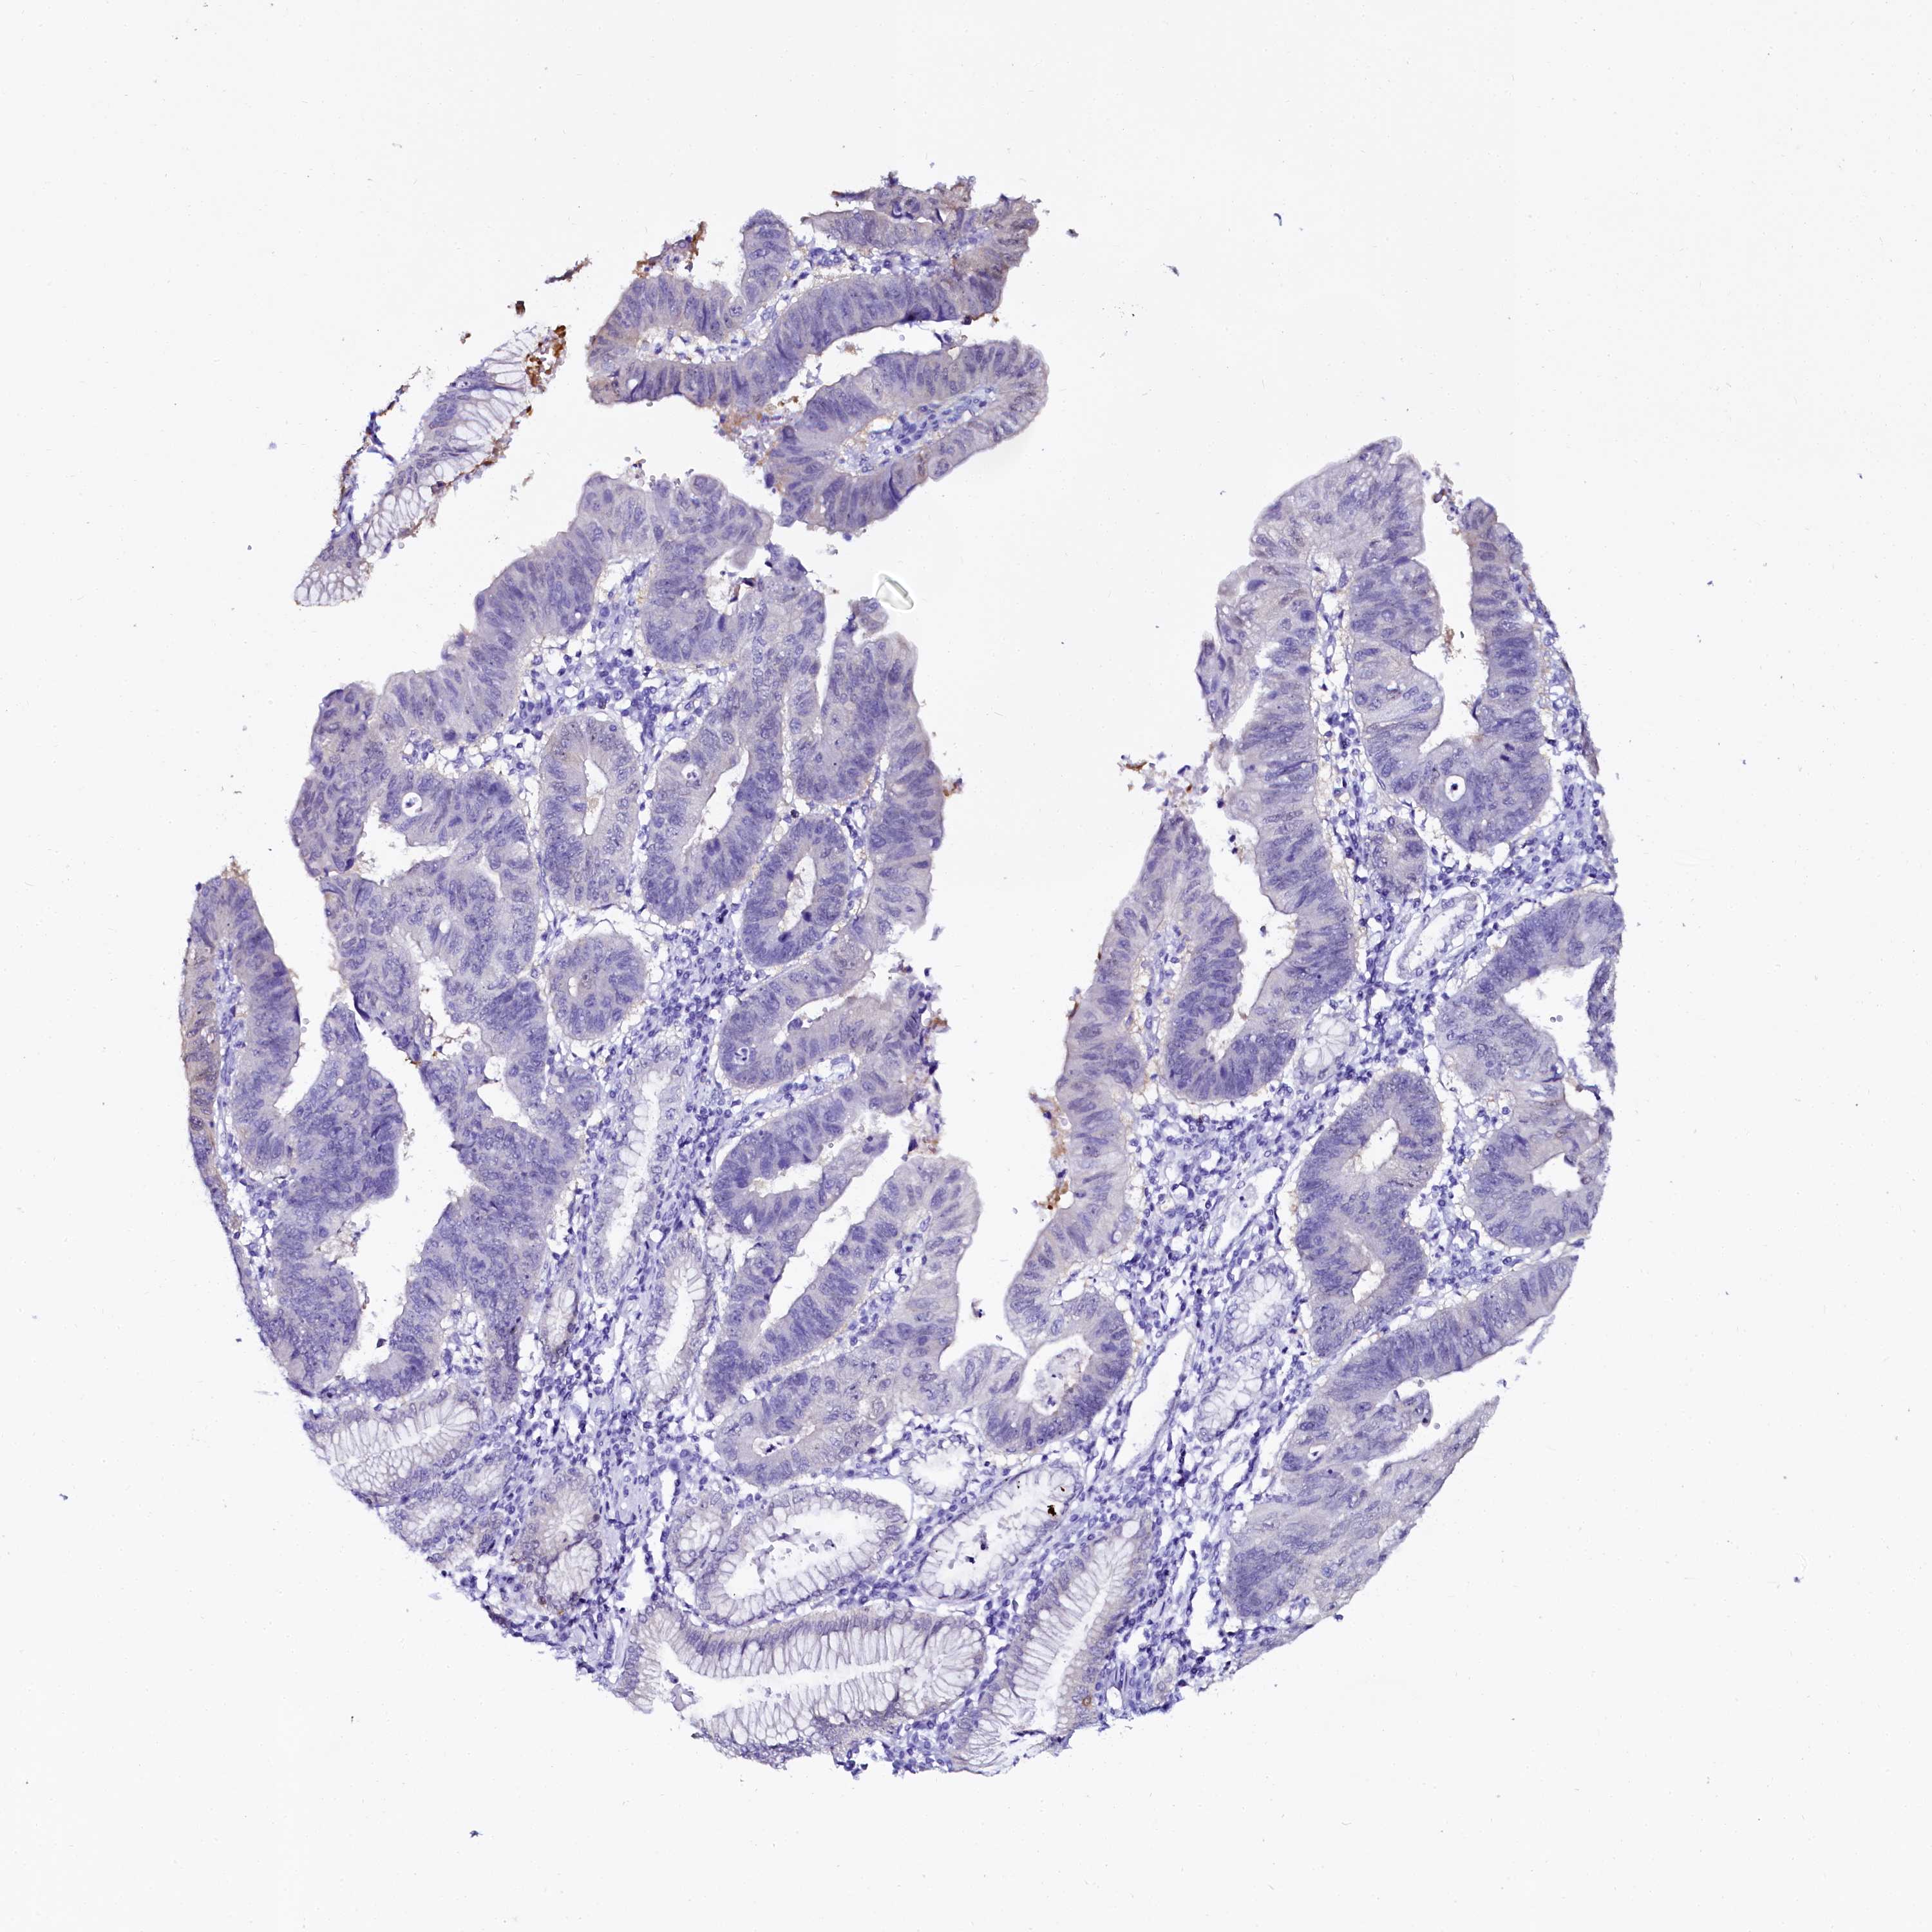

STOMACH CANCER - Protein expressioni

A mouse-over function shows sample information and annotation data. Click on an image to view it in a full screen mode. Samples can be filtered based on level of antibody staining by selecting one or several of the following categories: high, medium, low and not detected. The assay and annotation is described here.

Note that samples used for immunohistochemistry by the Human Protein Atlas do not correspond to samples in the TCGA dataset.

Antibody stainingi

Antibody staining in the annotated cell types in the current human tissue is reported as not detected, low, medium, or high, based on conventional immunohistochemistry profiling in selected tissues. This score is based on the combination of the staining intensity and fraction of stained cells.

Each image is clickable and will lead to virtual microscopy that enables deeper exploration of all samples and also displays staining intensity scores, fraction scores and subcellular localization as well as patient and tissue information for each sample.

Antibody HPA040260

Antibody HPA040621

Staining

High

Medium

Low

Not detected

Intensity

Strong

Moderate

Weak

Negative

Quantity

>75%

75%-25%

<25%

None

Location

Nuclear

Cytoplasmic/membranous

Cytoplasmic/membranous,nuclear

Adenocarcinoma, NOS